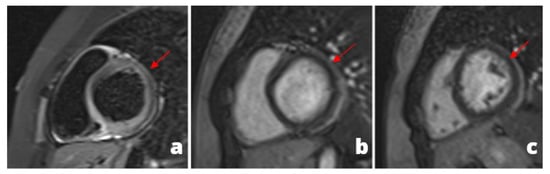

Figure 1.

A young adult presenting at emergency department with acute chest pain, subtle ST alterations in the lateral wall of the left ventricle and cardiac enzymes elevation. Cardiac MRI was performed 48 h later demonstrating edema in the inferior-lateral wall of the left ventricle (a) associated with hyperemia in early gadolinium enhancement (b) and post-inflammatory fibrosis using late gadolinium enhancement sequences (c).